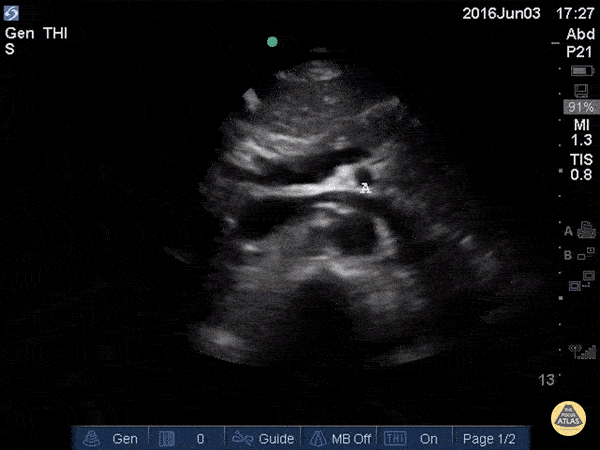

In the beginning of this clip we see several major structures in one view. From superficial to deep: liver, pancreas, splenic vein draining into the portal confluence, superior mesenteric artery in transverse (surrounded by a hyperechoic layer of fat creating the “mantle clock sign”), IVC with the left renal vein branching off, and the abdominal aorta. A vertebral body is visible at the bottom of the screen. As the probe is moved caudally, most of these vessels move out of plane and we are left following the course of the IVC and aorta inferiorly.